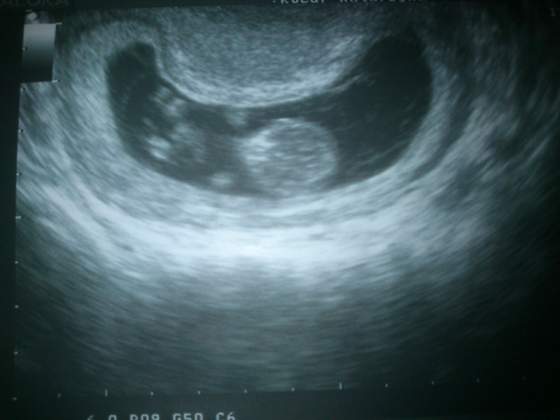

A to moj dzidzius zwiniety w fasolke - ale ruszal sie bo doktorkowi tetno uciekalo hehe

))